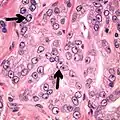

- Less specific findings.

- Mitoses (also seen in for example high-grade prostatic intraepithelial neoplasia (HGPIN) and prostate inflammation).[4]

-

Adenocarcinoma with two mitoses in reactive epithelium. -

Acinar adenocarcinoma with intraluminal blue mucin.